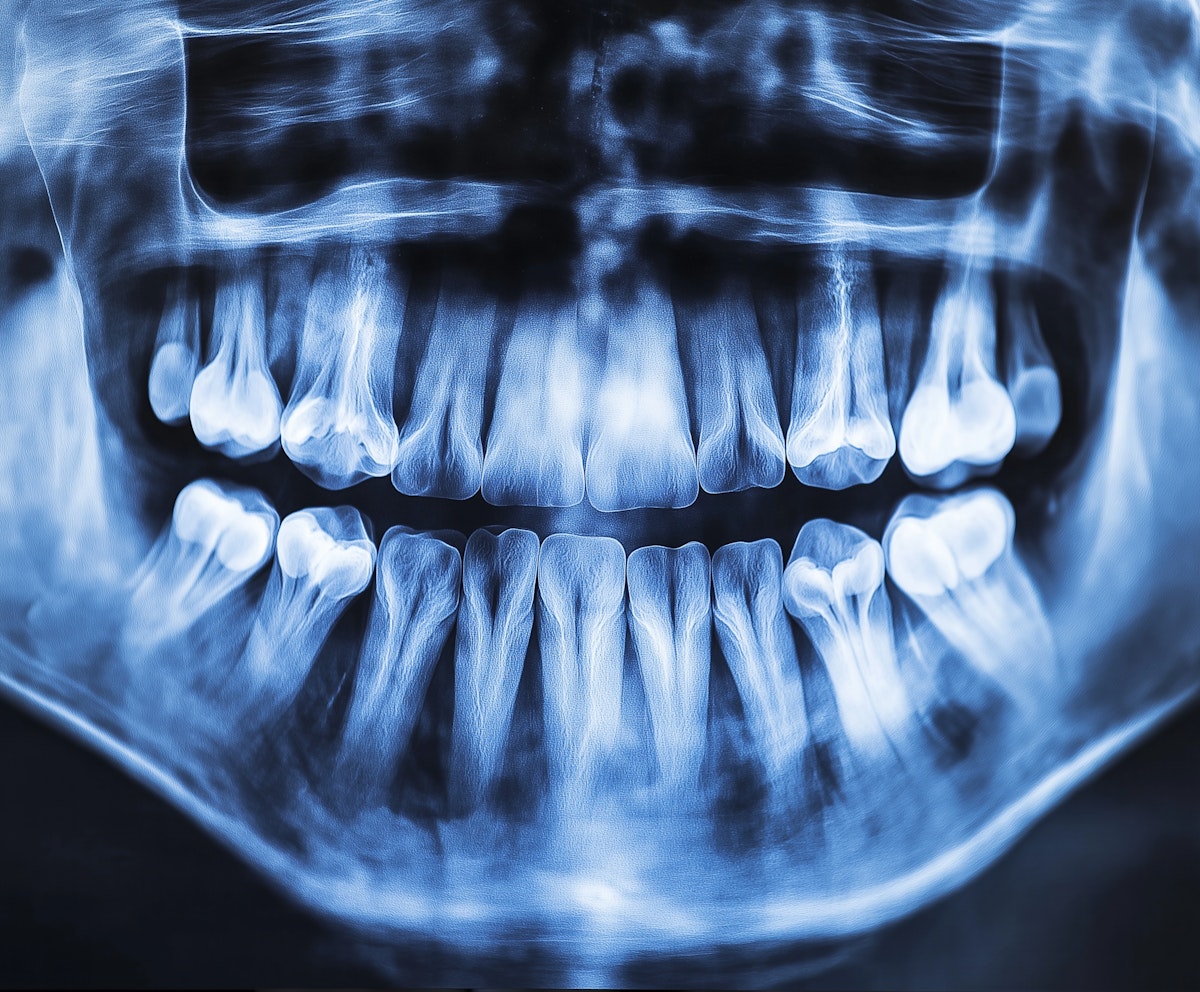

Free Consultation & X-Rays

Get a professional dental check-up in Woodland Hills at no cost! This includes a full consultation and X-rays to assess your oral health and detect any hidden issues early. No obligations—just expert care to keep your smile healthy and confident.